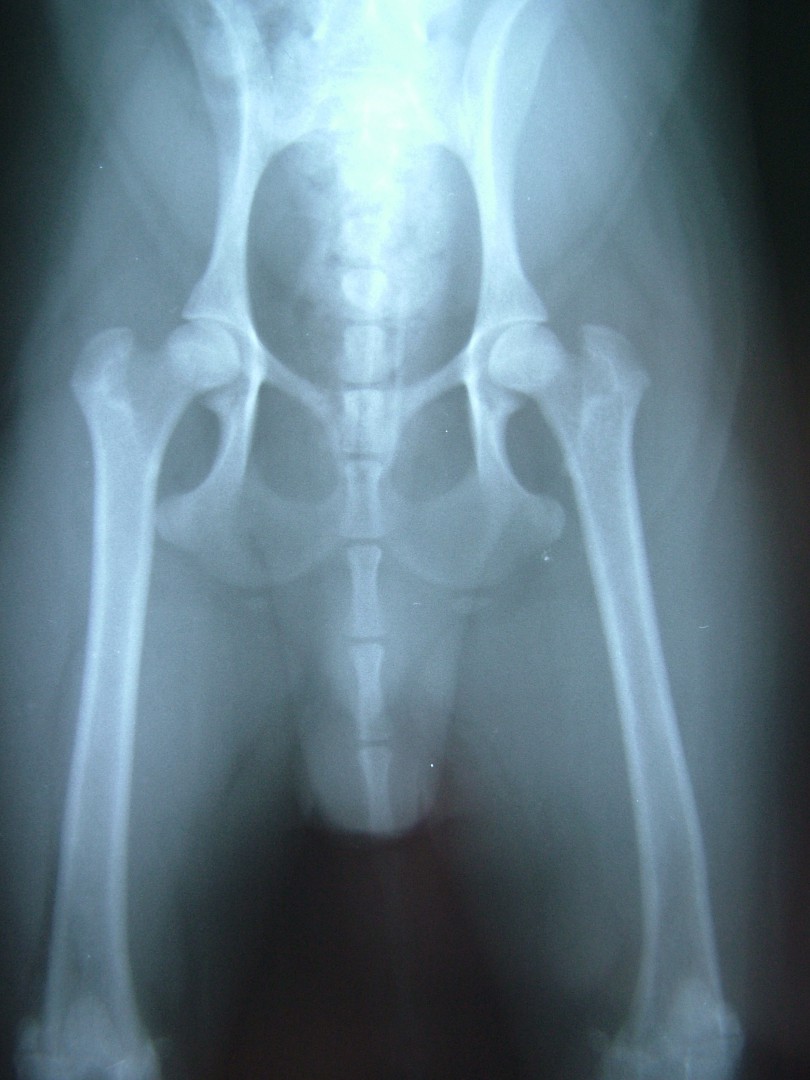

Legg-Perthes kór

Legg-Calve-Pertes kórnak nevezzük kistestű kutyákban a combcsontfej nem fertőzéses eredetű elhalását és az ebből adódó klinikai tüneteket.

A betegség szinte kizárólag kistestű kutyákban alakul ki, általában egyoldali, de mindkét combcsontfej érintettsége is előfordulhat. A combcsontfej elhalásának oka egy vérellátási zavar kialakulása. Örökletes jellege nem egyértelműen igazolt.

Az 1 év alatti kutyákban a hátsó lábon jelentkező enyhe fokú sántaság az első tünet, mellyel a tulajdonos általában az állatorvoshoz fordul. A csípőízület passzív mozgatására, rotálására az állat fájdalmat jelez. Az első tünetek megjelenésekor végzett klinikai vizsgálattal a csípőízületi fájdalom általában már a betegség gyanúját felkelti, ezért az ízület röntgen vizsgálatát is elvégezzük. Sok esetben azonban a klinikai tünetek megjelenése és a röntgen tünetek megjelenése nem esik egybe, ezért az enyhe fokú sántasággal járó korai szakaszban a betegség nem egyértelműen diagnosztizálható.

Ilyen esetben a 2-4 hét múlva elvégzett röntgen vizsgálat a Legg-Calve-Perthes kórt egyértelművé teszi.

A felvételen a combcsontfej csontos szerkezetének felbomlása, sok esetben a combcsontfej beroppanása látható.